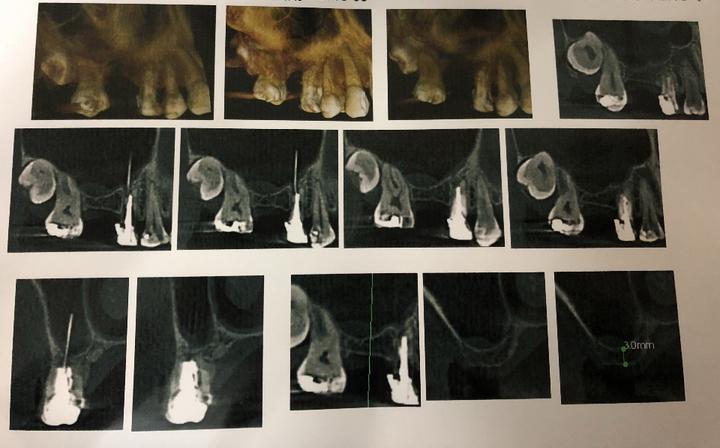

后来经拍CBCT确认是超填牙胶<strong>(图2)</strong>

患者  男  13岁,右下第二双尖牙根尖囊肿<strong>(</strong><strong>图3)</strong>也是因为牙胶尖的超填所致(曾于外院行根管治疗)。后经取出牙胶尖,完成根管治疗,根尖囊肿愈合<strong>(图4)</strong>。

图2  CBCT示超填牙胶尖

图3  超填牙胶导致根尖囊肿

图4  取出牙胶,根管治疗后一年,囊肿愈合